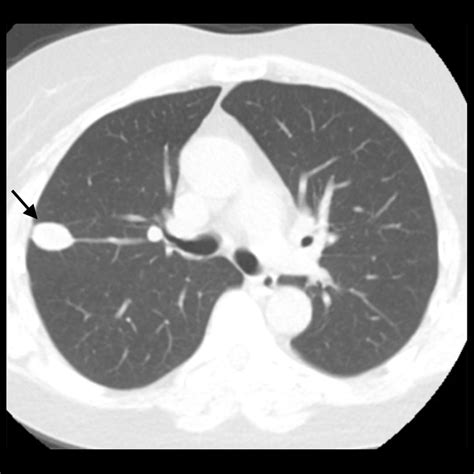

Understand what to expect during a CT chest without contrast. This diagnostic imaging procedure provides detailed views of the lungs, heart, and chest cavity without using dye. Learn how this non-invasive scan aids in detecting nodules, infections, and pulmonary issues while ensuring patient safety and preparation for your next medical evaluation.

Read full article: Ct Chest Without Contrast